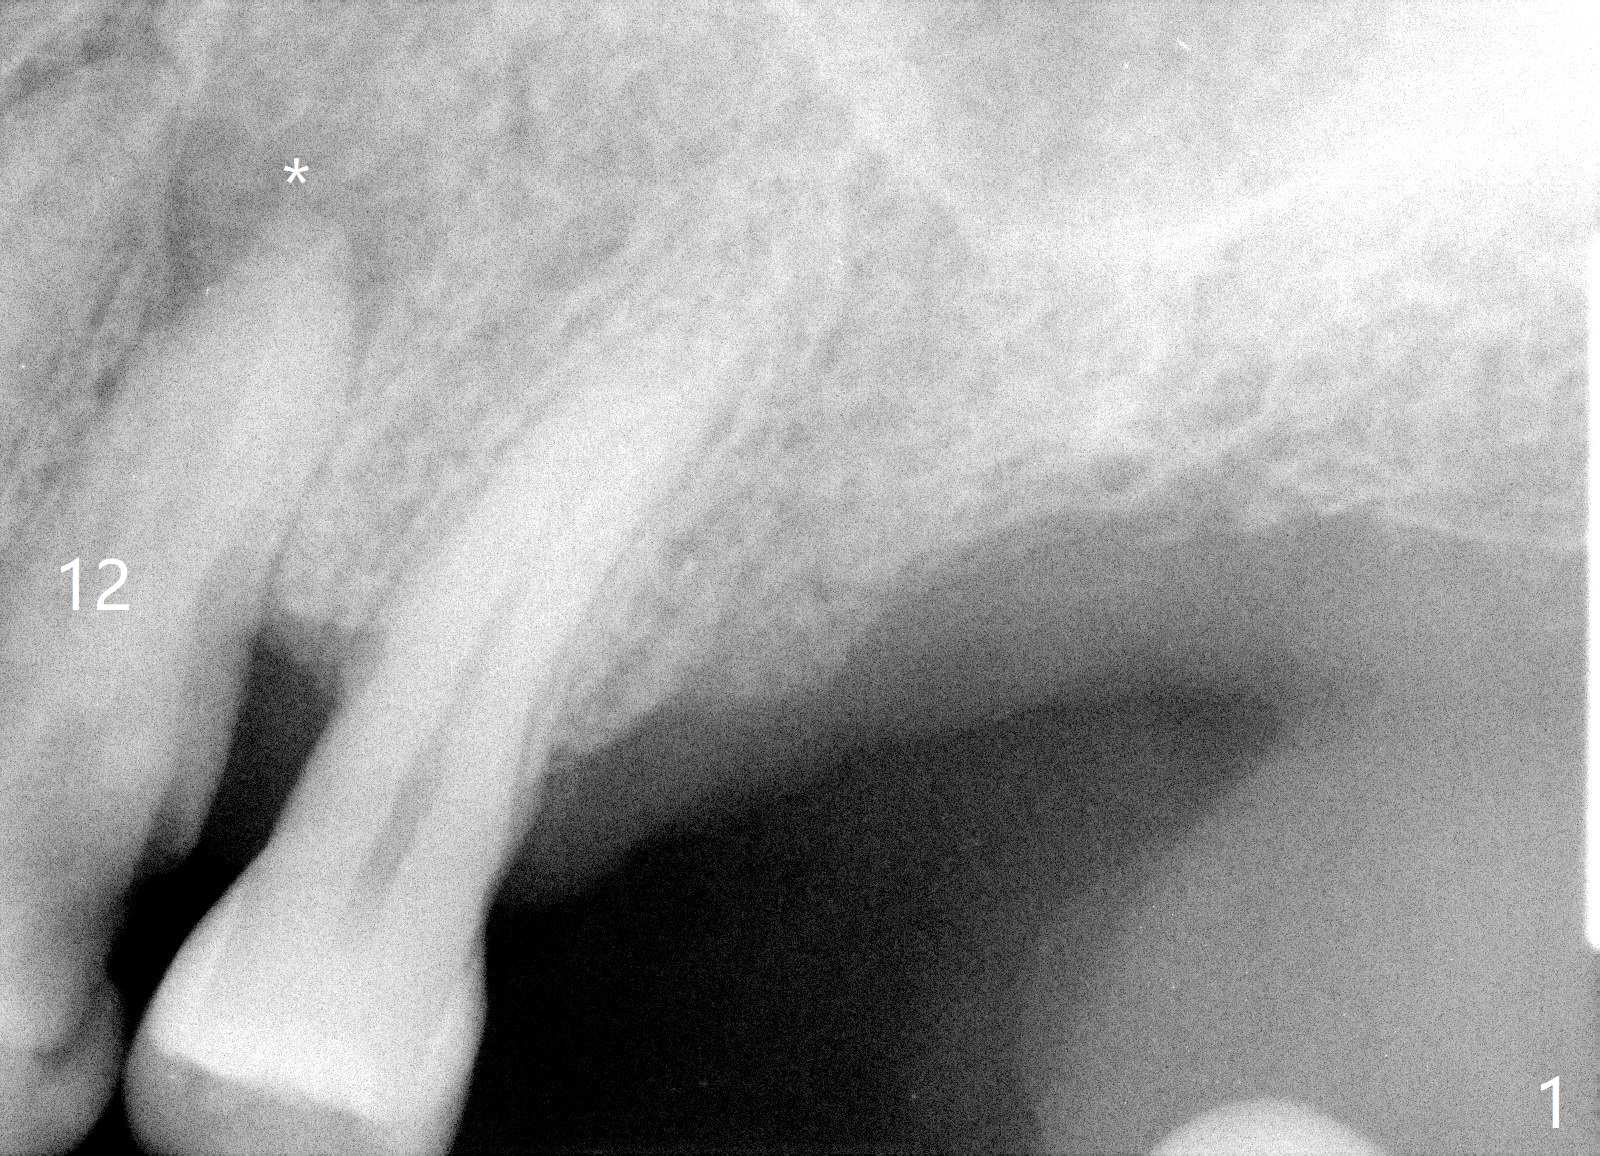

A 61-year-old man with chronic periodontitis presented to clinic for several implant placement (#3 10 14/15 18 30). For the tooth #12 (Fig.1), RCT was rendered (Fig.2). The tooth is non-salvageable 4.5 years post-treatment (Fig.3). Uneven bone loss mesiodistally makes implant placement challenging (Fig.4). A long implant will be used with ~3 mm subcrestal (mesially) and ~3 mm supracrestal (distally). A 3.5 or 4.0x13 mm implant will be placed subcrestal palatally and supracrestal buccally (Fig.5).